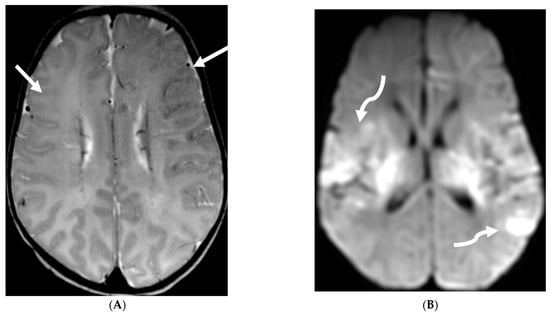

Anti-MOG antibody associated demyelination (MOGAD) frequently presents as Acute Disseminated Encephalomyelitis (ADEM) in children and opticospinal involvement in young adults [105]. Bilateral but asymmetric T2 hyperintense lesions occur in thalamus, pons and cerebellar peduncles are common in children [106]. Optic nerve involvement typically presents as a long segment with anterior predominance, in contrast to the posterior predominance seen in Neuromyelitis Optica Spectrum Disorders (NMOSD) and the short segment involvement characteristic of Multiple Sclerosis (MS) [106].

LME has been shown to present early in the disease course and is much more common in children (33%) compared to adults (8%) [107]. Gadde et al. found that 8% of pediatric MOG antibody-associated demyelination cases had only LME without any other central nervous system manifestation. LME when present can be particularly helpful in differentiating from NMOSD [106]. Furthermore, Valencia-Sanchez et al. reported a significant association between LME and cerebral cortical encephalitis in MOG antibody-associated disease. This finding suggests that LME may be an important marker for cortical involvement and potentially more severe disease (Figure 21) [108].

Figure 21.

Sagittal T2 (A,B), axial FLAIR (C), axial T2 cervical spine (D) at the level of C7 vertebral body and Axial T2 orbits (E): 12-year-old girl presented with right focal motor seizure and left temporal lobe slowing on electroencephalogram (EEG). Right eye vision loss and irritability. Ill-defined areas of signal abnormalities are identified within the RIGHT mesial temporal lobe and bilateral medulla (white arrows). FLAIR hyperintensity is identified on the left central sulcus (black arrow). Small focus of signal abnormality is seen on the right side of the cord at the 7th cervical vertebra (C7) (dashed arrow). There is also bilateral papilledema (arrowheads). Post contrast axial T1 (F,G), axial T1 orbits (H) and axial T1 cervical spine at C7 (I): Asymmetric LME (black arrows) predominantly involving the left cerebral hemisphere, with minimal right parietal involvement is seen. Ill-defined enhancement in the right mesial temporal lobe, and right greater than left medulla (white arrows) corresponds to the signal abnormality. There is right greater than left, optic nerve enhancement (curved arrow). Single small enhancing lesion in the spinal cord on the right at the level of C7 corresponds to the signal abnormality (dashed arrow). Features favor a demyelinating process. MOG antibodies were positive at 1:20 in keeping with Myelin oligodendrocyte glycoprotein (MOG) antibody disease (MOGAD).